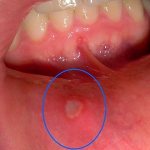

На ранней стадии пациенты жалуются на покалывание губ и слизистой, зуд, неприятные пощипывания, покраснение, отечность. Во время глотания, жевания часто возникает боль. Так проходит первая стадия, после которой развивается герпес в острой форме.

При остром течении заболевания активно формируются пузырьки, которые спустя несколько дней самопроизвольно вскрываются. На поверхности элементов высыпаний появляется желтоватая корочка. При разговоре герпес может доставлять болезненные ощущения, принимать пищу практически невозможно. Полость рта высыхает, из-за чего человек постоянно испытывает сильную жажду.

На финальной стадии заболевания эрозии обрастают плотными корочками. Старайтесь не сдирать их, поскольку ранки начнут кровоточить, станут проводником для попадания инфекции. Если все в порядке, то через 2 недели после появления первых высыпаний происходит полное заживление тканей без рубцевания. При попадании инфекции ранки могут гноиться. Про атопический хейлит на губах узнайте тут.

Герпесные элементы появляются обычно возле верхнего неба, десен, а стоматит «выбирает» мягкие части рта – то есть язык, щеки, губы. Это не 100% закон, но использовать его в рамках самостоятельной диагностики можно. Что касается характера сыпи, то герпес во рту – это всегда сначала пузырьки, а потом ранки, в то время как стоматит проявляется сразу в виде ранок.

Патологический процесс имеет конкретную локализацию и обусловленную ею симптоматику. На деснах герпес начинается с лихорадочного синдрома, который продолжается в течение нескольких дней. После понижения температуры возникает характерная сыпь на деснах. Чувствуется дискомфорт в зонах воспаления, десны начинают кровоточить в процессе чистки зубов. Наблюдается повышенное слюноотделение, язык покрывается плотным налетом, воспаляются губы. Симптомы напоминают зубную боль, которая становится более выраженной в процессе жевания. Герпес на внутренней стороне щек проявляет себя высыпаниями, которые сопровождаются гиперемией, жжением.